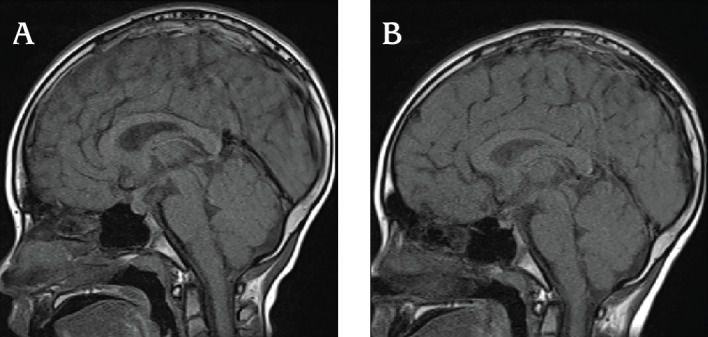

儿童期发作的淋巴细胞性漏斗状尿路垂体炎(LINH)很少报道。通过垂体活检进行病理学评估对于明确诊断LINH是必要的。然而,垂体活检是一种高度侵入性的手术。最近,抗Raphilin-3A抗体(RPH3A-Ab)已被报道为成人LINH的一种有前途的诊断标志物;然而,在儿科人群中很少有这样的报道。我们报告了一例患有中枢性尿崩症(CDI)的8岁男孩,根据RPH3A抗体阳性,他被临床诊断为LINH。他被诊断为CDI,使用脱水测试结合去氨加压素给药。血清和脑脊液肿瘤标志物均为阴性,T1加权磁共振成像(MRI)显示垂体后叶缺乏高信号强度,垂体柄增大。垂体前叶功能检查未发现异常。由于其侵袭性,未进行垂体活检,并开始使用去氨加压素治疗。CDI发病三个月后,患者RPH3A-Ab检测呈阳性。CDI发病9个月后进行的MRI检查显示垂体柄增大有所改善,临床过程证实了我们对LINH的诊断。RPH3A-Ab可能是儿科人群中LINH的早期诊断工具。

Childhood-onset lymphocytic infundibuloneurohypophysitis (LINH) has rarely been reported. Pathological evaluation via pituitary biopsy is necessary for a definitive diagnosis of LINH. However, pituitary biopsy is a highly invasive procedure. Recently, anti-rabphilin-3A antibody (RPH3A-Ab) has been reported as a promising diagnostic marker for LINH in adults but.there are few reports of this association in the pediatric population. We report the case of an 8-year-old boy with central diabetes insipidus (CDI) who was diagnosed clinically with LINH, based on RPH3A-Ab positivity. He was initially diagnosed with CDI using a water deprivation test combined with desmopressin administration. Serum and cerebrospinal fluid tumor markers were negative, and T1-weighted magnetic resonance imaging (MRI) revealed the absence of high signal intensity in the posterior pituitary gland and an enlarged pituitary stalk. Anterior pituitary function tests revealed no abnormalities. No pituitary biopsy was performed because of its invasive nature, and desmopressin treatment was initiated. Three months after the diagnosis of CDI, the patient tested positive for RPH3A-Ab. MRI performed nine months after CDI diagnosis revealed amelioration of the pituitary stalk enlargement, and this clinical course corroborated our diagnosis of LINH. RPH3A-Ab may be useful as an early diagnostic tool for LINH in the pediatric population.